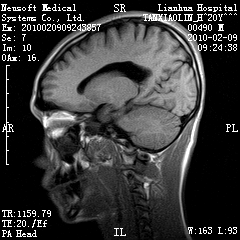

20岁男性患者,平时偶有头痛而无其他不适,现因持续头痛服药后无缓解而来院就诊。

松果体区占位继发轻度脑积水?该患者有ct资料,我已发上。